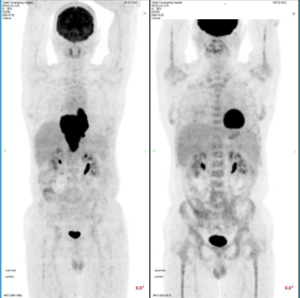

这个疗程就比较麻烦,老爸反复低烧跑医院,入院,出院。今天五疗入院,做了pet,真如洪飞老师所说,我爸主管医生的判断完全正确,1分,完全缓解。肿瘤一点都没有了,也没有代谢值高的地方。之前确实虚惊一场,这真的是天大天大的好消息。总算是放下心来了